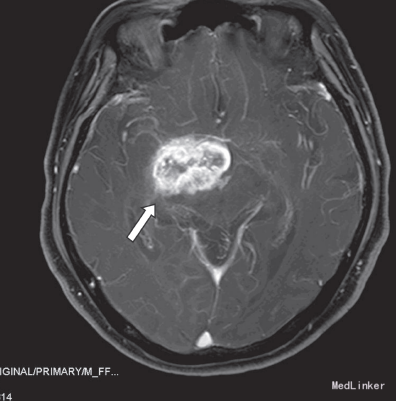

给予脱水、阿司匹林抗血小板治疗3天后病情无改善。再行头部增强MRI示:1、右侧颞叶及邻近的丘脑区可见一长增强后明显强化,高级别胶质瘤可能大;2、双侧半卵圆中心内多发缺血梗塞灶。在全麻下行开颅手术,术中见:右侧基底节区见异常脑组织,色黄,质韧,血供不丰富,与周围脑组织分界不清,前颅底见一包块大小约1.5cm×2cm ×2cm,色红,血供丰富,余无特殊。行“开颅右侧基底节区、第三脑室及前颅底占位切除术+颅内减压术+颅内压探头置入术”,术后病检示:间变型少突-星形细胞瘤(WHO,Ⅲ级)。术后给予脱水降压及营养神经治疗,复查头部CT示:右侧颞叶术区见积液、积气影,局部见出血灶,血肿大小约2.2×1.4cm,周围少许脑组织水肿。术后三天患者神智逐渐恢复,反应仍迟钝,左上肢肌力恢复至2 级,下肢肌力仍为2+级。10天后患者出现少量咳嗽咯痰,痰不易咯出,查体体温正常,双肺均闻及少许湿罗音,复查血常规示白细胞计数14.30×109/L,中性分叶核粒细胞百分率85.3%,(未行影像学检查),考虑肺部感染,给予他唑仙抗感染,治疗1 天后咳嗽咳痰无明显好转。2天后患者突发意识障碍,呈深昏迷,叹气样呼吸,血压及氧饱和度测不出,双侧瞳孔散大固定,直径0.6cm,对光反射消失,经积极抢救无效死亡。